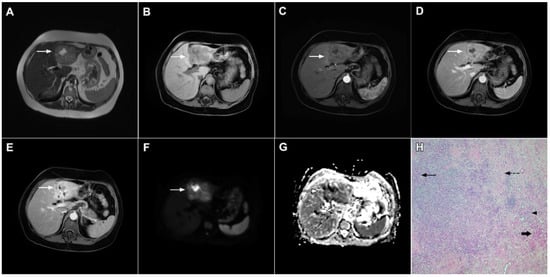

Figure 7.

Mucin-rich mass-forming cholangiocarcinoma in a 78-year-old woman. The axial T2-weighted image (A) shows the lobulated hyperintense lesion (arrow) located in the subcapsular region of liver segment IVB, which is associated with capsular retraction. On the plain T1-weighted image (B) the lesion (arrow) is hypointense. In the arterial phase (C), ring enhancement can be seen with slight “ragged” central enhancement in the portal venous (D) and delayed phase (E). On DWI, diffusion restriction is noted on the periphery of the lesion (arrow) while no restriction is seen in the central part of the tumor (F). Corresponding ADC map showing targetoid appearance of the lesion is shown on (G). Hematoxylin and eosin (H&E) staining (H) showed cholangiocarcinoma (arrows) adjacent to normal liver parenchyma (dashed arrow); original magnification ×40.